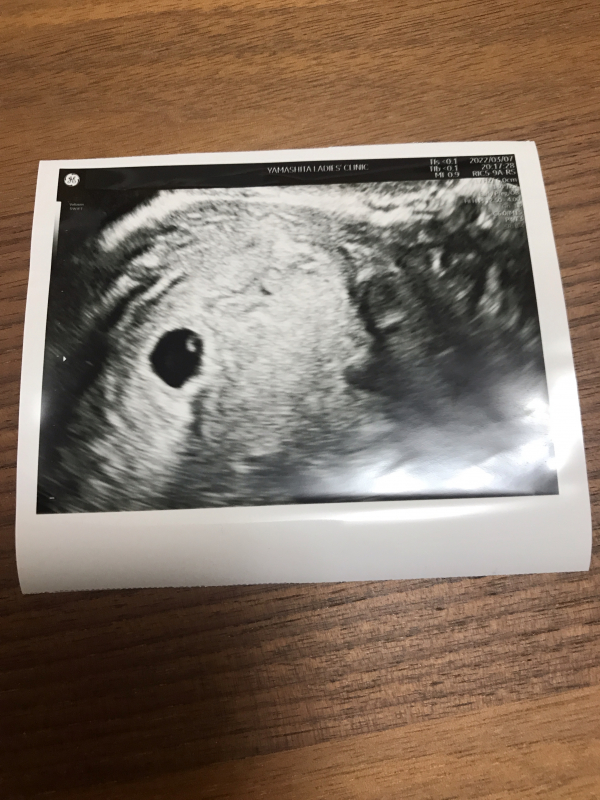

5週5日で胎嚢確認、卵黄嚢が確認出来たのですが、BT14の判定日の血液検査結果が、hcg888で、先生が4週5日にしたら数値が少し低いとおっしゃられました。標準はどのくらいなんでしょうか??継続はまだわからないとのことで、チャンスはあるとは言われたもやもやする回答でした。胎嚢サイズは測ってもらえず、みた感じで5週5日相当の大きさだとゆわれました。hcgが少し低くても可能性はあるのでしょうか?ちなみに4週5日では胎嚢確認出来なかったのに、1週間後すごい勢いで成長したのでしょうか??5週5日のサイズは平均どのくらいですか??

胎嚢のサイズがわかりませんが、1週間で胎嚢や卵黄嚢が見えていますから、成長したのではないかと思います。